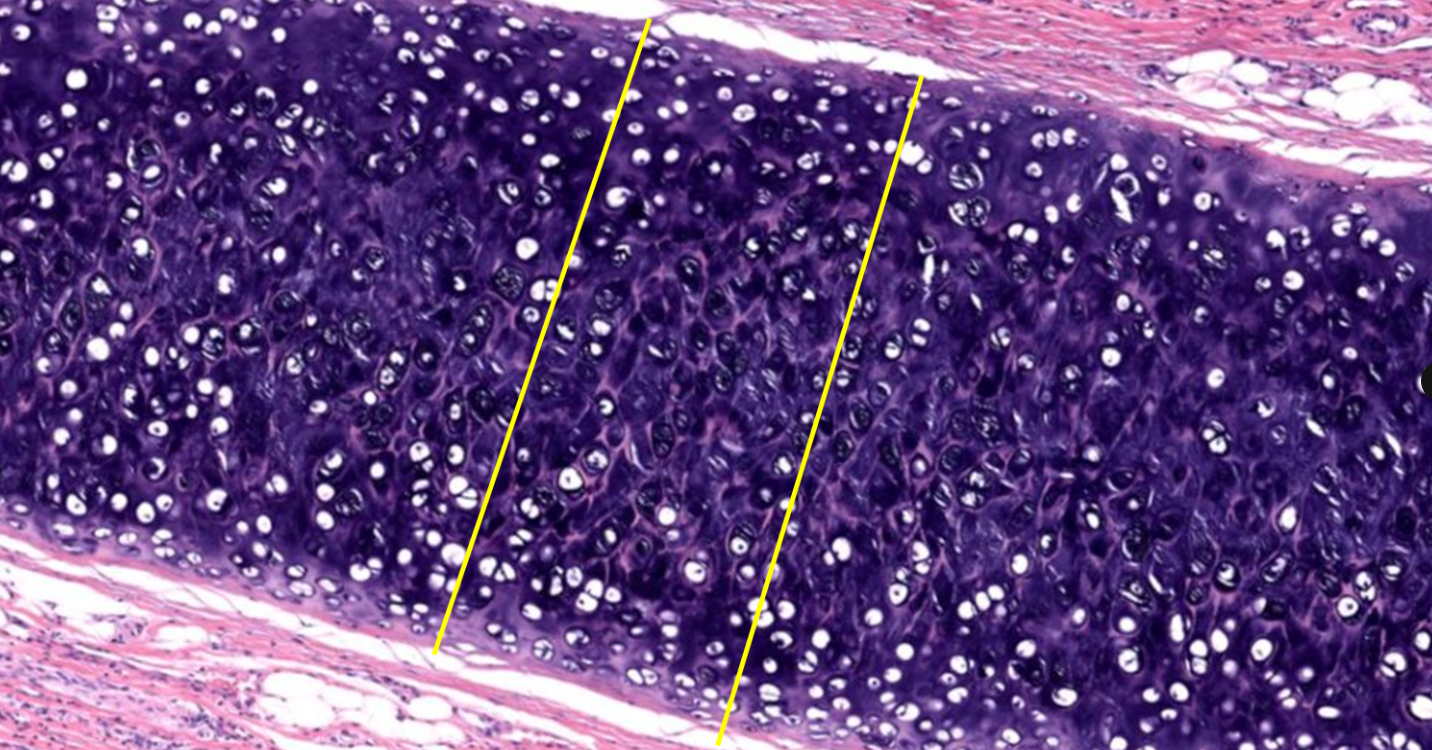

Cartilagem hialina